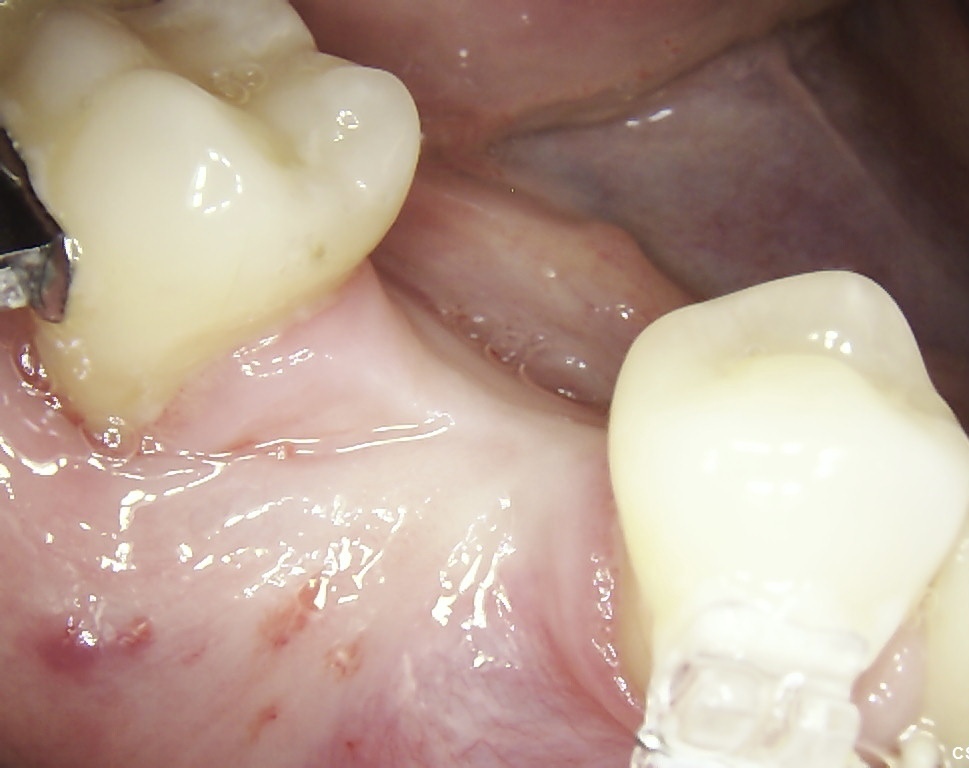

Before starting orthodontic treatment, the teeth must be healthy, the

periodontal tissues must be free of inflammatory changes. In addition, it is

very important to master meticulous oral hygiene.

After 6 months of successful

orthodontic treatment, we were finally able to place the implant and the

provisional crown. After 4 months of ingrowth, aligners were removed and a full

ceramic crown was placed. The treatment was successfully completed!✋🏽😉